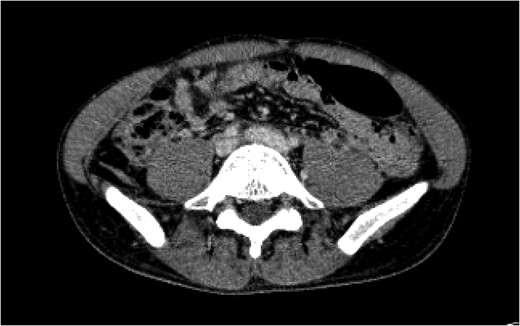

Figure 1:

A CT of the abdomen and pelvis taken on arrival (Day 1) showed a blush of contrast at the bifurcation of the common iliac veins.